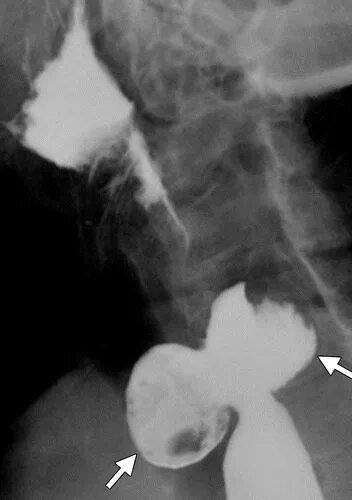

Дивертикул трахеи